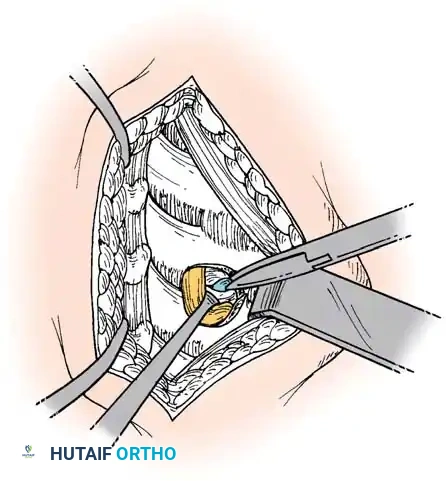

Step 2: Annulotomy and Discectomy

Self-retaining retractors are placed beneath the elevated medial borders of the longus colli. A rectangular annulotomy is performed using a #11 blade. The disc material is systematically removed using pituitary rongeurs and curettes.

Step 3: Decompression

The posterior longitudinal ligament (PLL) is carefully identified and often resected to ensure no extruded disc fragments remain in the epidural space. High-speed burrs and Kerrison rongeurs are utilized to resect posterior osteophytes and decompress the uncinate processes bilaterally, ensuring the exiting nerve roots are entirely free.

Step 4: Endplate Preparation and Fusion

The cartilaginous endplates are meticulously decorticated using a curette or burr to expose bleeding subchondral bone, which is critical for arthrodesis. Care must be taken not to breach the structural integrity of the endplate to prevent graft subsidence.

An appropriately sized structural allograft, autograft, or synthetic cage packed with osteoinductive material is impacted into the disc space under gentle cervical traction. An anterior cervical plate is then secured with screws into the adjacent vertebral bodies to provide immediate biomechanical stability.